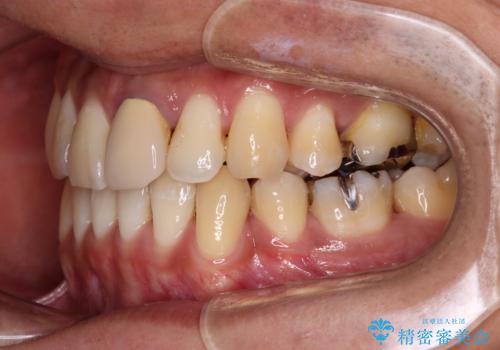

- 下顎の八重歯を気にして来院された患者様です。

左下以外、3本の第一小臼歯が既に抜去されており、左下は八重歯になっている状態でした。

左下の八重歯は手前に傾斜していたため、インビザラインによる抜歯矯正が可能と判断し、後方にある第一小臼歯を抜歯してインビザラインにて矯正治療を行うこととしました。

ワイヤー矯正と比較すると、八重歯が後方に傾斜した仕上がりとなりましたが、患者様ご希望のインビザラインにて十分な歯列を達成することができました。